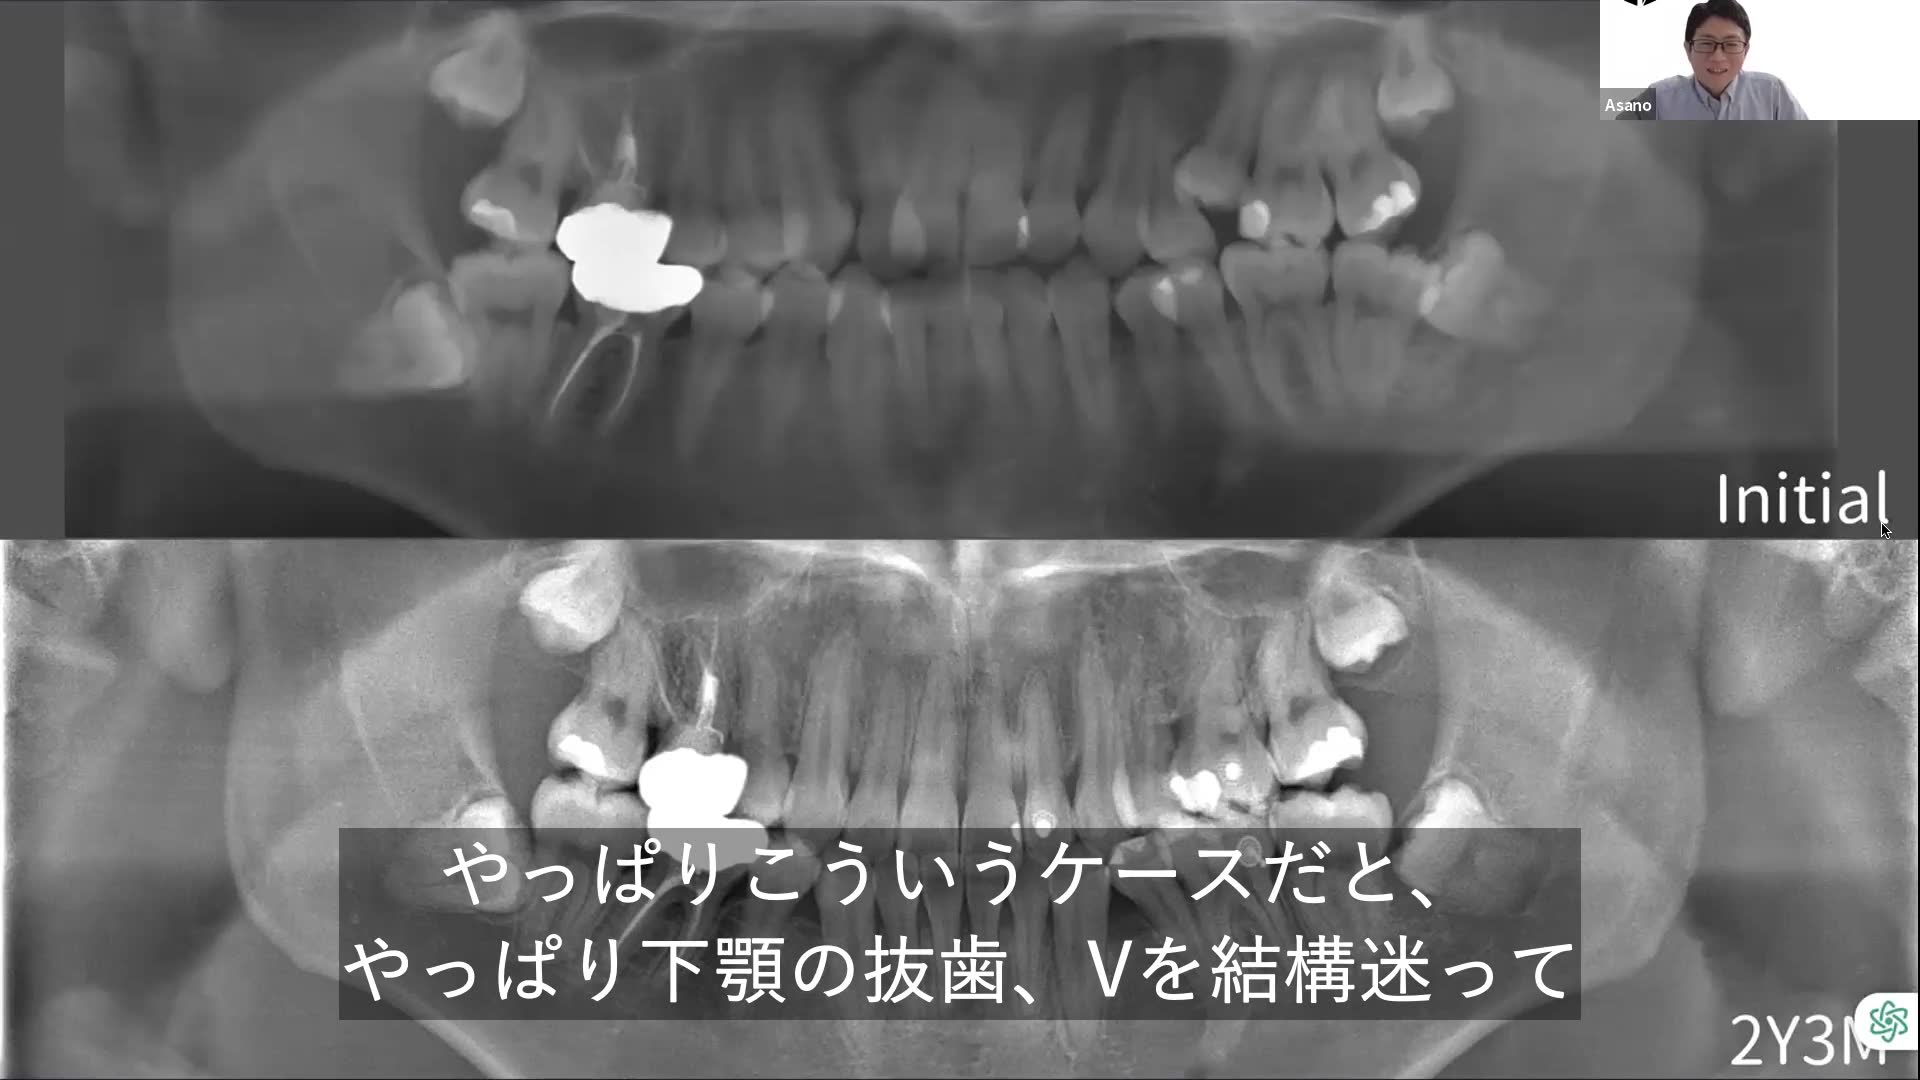

下顎の抜歯Vについて